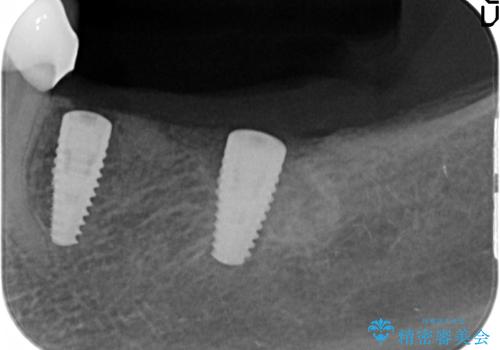

- 91万円(ストローマンインプラント×2・骨造成・チタンカスタムアバットメント×2・フルジルコニアクラウン×3)費用は治療当時の料金となります

インプラントを埋入することで入れ歯のように取り外しをする必要がなくしっかりと噛めるような状態になり、大変治療結果に満足していただくことができました。